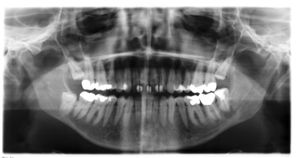

menschliches Gebiss mit 32 Zähnen (Röntgenbild); bis auf Zahn 38 (im Bild rechts unten) sind die Weisheitszähne noch nicht durchgebrochen

Zur Vermeidung von Missverständnissen werden die Zähne des Menschen in der Zahnheilkunde durch die Gebissformel eindeutig bezeichnet. Das Gebiss wird dazu in 4 Quadranten unterteilt, d.h. pro Kiefer erfolgt die Teilung zwischen den mittleren Schneidezähnen. Diese Quadranten dienen als erste Ziffer der Zahnbezeichnung:

• oben rechts = 1 (bei Milchzähnen: 5)

• oben links = 2 (bei Milchzähnen: 6)

• unten links = 3 (bei Milchzähnen: 7)

• unten rechts = 4 (bei Milchzähnen: 8)

Die einzelnen Zähne werden dann jeweils von vorn beginnend durchnummeriert. Der linke untere Weisheitszahn trägt somit die Bezeichnung 38 (sprich: drei-acht), während der erste obere linke Schneidezahn als 21 (sprich: zwei-eins) bezeichnet wird.

Das F.D.I.-Schema, welches seit 1970 von der Fédération Dentaire International empfohlen wird, ist somit computergerecht und wird derzeit weltweit am häufigsten genutzt.

Insbesondere ist darauf zu achten, dass in der Zahnmedizin - wie auch in der Allgemein-Medizin - das System grundsätzlich aus der Sicht des Patienten geschildert wird (Merke: "Die rechte Hand ist immer und aus jeder Blickrichtung die rechte Hand"). Das heisst, während beispielsweise Zahn 38, der linke untere Weisheitszahn, beim Patienten in der linken Mundhälfte liegt, wird die Linke vom gegenübersitzenden Behandler als rechts wahrgenommen.